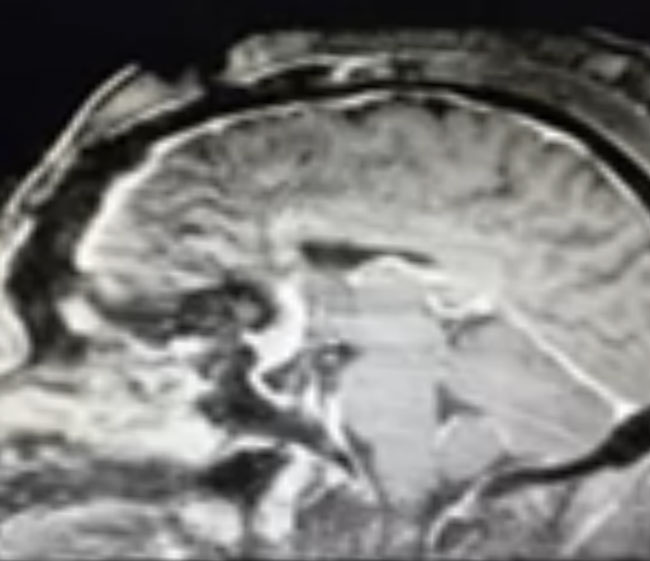

The patient underwent a bifrontal craniotomy and near total removal of the tumor. Because the frontal sinuses were small, it was possible to perform the craniotomy without violating the frontal sinuses. The tumor was removed nearly completely except for a small portion that was stuck to the optic nerves and the anterior communicating artery complex (Figure 2). Postoperatively, the patient immediately noted that her vision had been restored to normal. She was discharged on postoperative day 2. The small remaining tumor will be followed, and may be treated with stereotactic radiosurgery in the future.

Meningiomas can arise from any meningeal tissue within the brain or spinal canal. They are almost all benign tumors. This particular tumor arose from the planum sphenoidale, the flat posterior midline part of the sphenoid bone, a region that forms part of the floor of the anterior cranial fossa. Sometimes these tumors can be removed safely in entirety, depending on how adherent the tumor is to the deep surrounding structures, in particular, the optic nerves, the optic chiasm, and the anterior communicating artery. In this case, the tumor was quite adherent to these most posterior and inferior structures, so it was decided not to risk dissecting this last remaining piece of tumor off these critical structures.